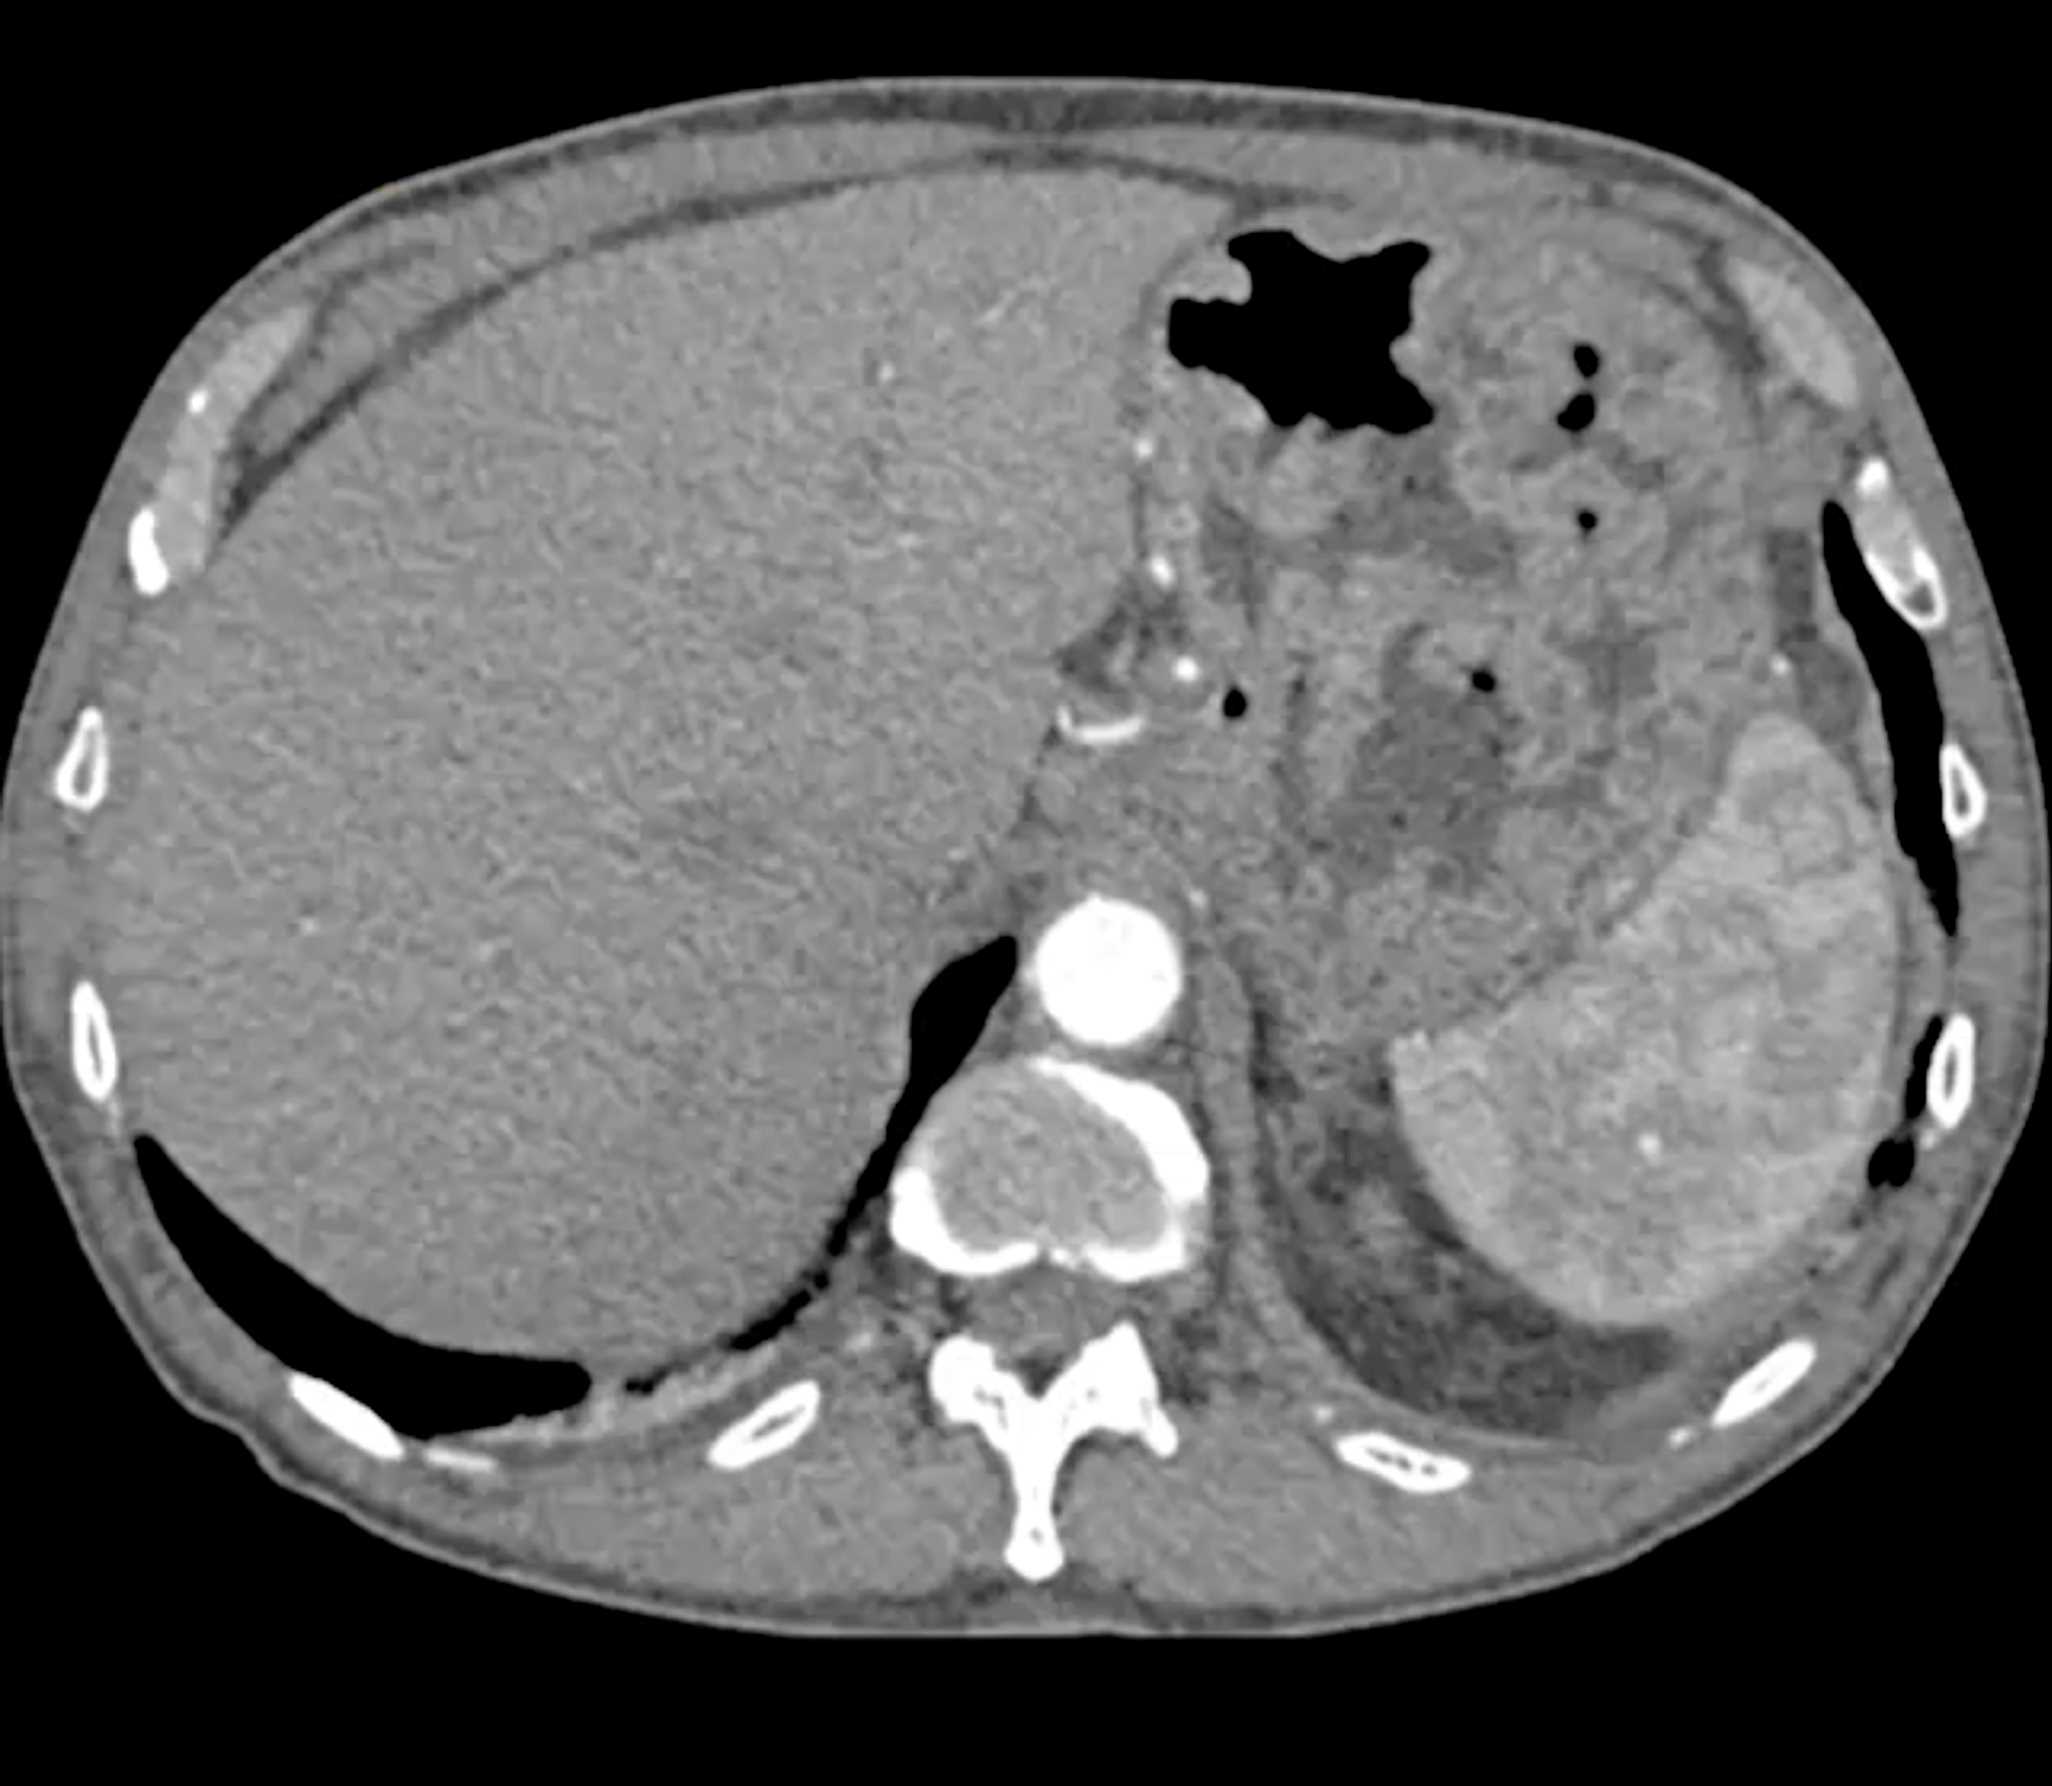

Lagre Gastric GIST Tumor